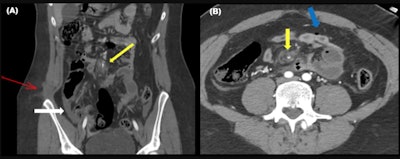

Abdominal wall hernias occur because of the shearing forces through the myofascial layers of the abdominal wall during the sudden deacceleration and the high increase in the intraabdominal pressure. They occur through the weakest anatomical sites of the abdominal musculature. Multiplanar reformation should be performed to increase sensibility.

"Although they are misdiagnosed clinically, their presence indicates the violence of the accident and they are associated with a high risk of surgical intraabdominal injuries; either herniated intraabdominal structures or structures far from the herniation site," they explained. "Other abdominal wall injuries include soft tissue contusion or direct muscle rupture."

Bowel and mesenteric injuries

In motor vehicle collisions bowel injuries are more likely to be ischemic than in other blunt trauma or penetrating trauma, the researchers continued.

"They occur because of shearing forces at the junction of mobile and fixed bowel plus the high intraabdominal pressure caused by the entrapment of intestine loops over and above the lap belt," they pointed out. "These mechanisms can cause a bucket-handle tear which is an injury in which the mesentery avulses off a bowel loop. Mesenteric injury can be misdiagnosed first causing a delay in surgical intervention."

These kinds of ischemic injuries are more frequent in the ileocecal region and proximal jejunum. In the Madrid facility's database, the small intestine was damaged more frequently than the colon.

The most specific CT signs are bowel mural discontinuity, pneumoperitoneum, or active mesenteric bleeding.

"Free oral contrast is considered by some authors as the most specific sign of blunt trauma of the bowel and mesentery," they wrote. "Nevertheless, a retrospective single-center study found that hyperenhancement of the bowel adjacent to a hypoenhancing segment would be the most specific sign in a routine trauma CT exam."

Free fluid or interloop fluid, bowel wall thickening, or mesenteric contusions are relatively less specific signs, but they are more prevalent, according to the authors.